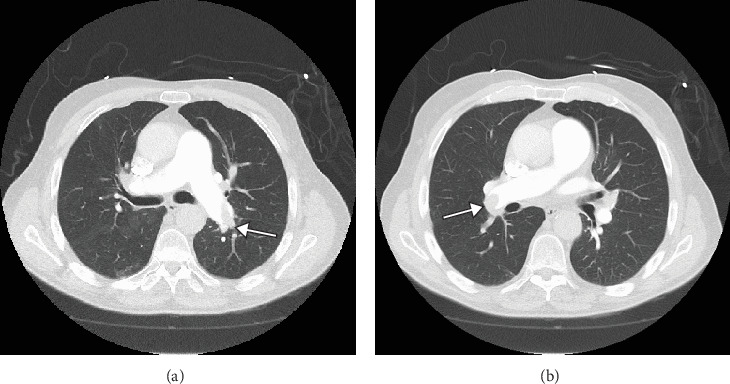

May-Thurner syndrome (MTS) is characterized by the formation of an intravenous scar or venous "spur" resulting from chronic pulsatile compression of the left common iliac vein (LCIV) by the right common iliac artery (RCIA) against the fourth or fifth lumbar vertebral body. This pulsatile compression creates a flow-limiting stenosis of the LCIV, leading to increased intravenous pressure in the veins draining the left lower extremity (LLE). Consequently, this elevated venous pressure manifests as a spectrum of chronic symptoms including unilateral LLE edema, pain, tenderness, warmth, skin inflammation, and discoloration, along with pelvic symptoms such as sensation of fullness and dyspareunia. Furthermore, MTS significantly elevates the risk of venous thromboembolism characterized by LCIV deep vein thrombosis (DVT) and potentially fatal pulmonary embolism (PE). Treatment options for MTS range from anticoagulant therapy to, in severe cases, operative intervention. Herein, we present a case of a 79-year-old male with MTS who experienced a near-fatal DVT that led to PE, compounded by a chronically distended urinary bladder, necessitating immediate operative removal of the PE.